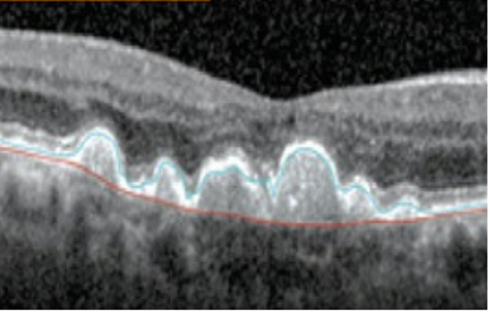

Through photobiomodulation, the retinal cells are rejuvenated, facilitating improved cell function within the macula. In cases of dry AMD, this not only slows progression, but studies have also shown that photobiomodulation can reverse some aspects of the disease - such as drusen formation, as seen below.

Baseline

After 12 months

As well as improving and maintaining vision, photobiomodulation reduces the volume of drusen at the macula, and over 24 months, drusen thickness had reduced by 24% on average.